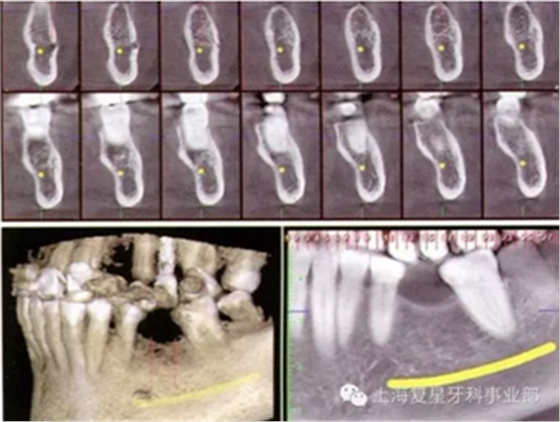

圖3a:左側(cè)下頜骨區(qū)CBCT掃描

一位55歲的健康女性,要求進(jìn)行下頜磨牙的修復(fù)。她的主訴是:左側(cè)下頜第一磨牙(36#牙)由于幾年前根管治療失敗而拔除導(dǎo)致磨牙缺失。經(jīng)過包括臨床和圖片分析的完整診斷評(píng)估后,使用ProMax(普蘭梅卡;圖1和3a)三維掃面儀對(duì)左邊的下頜骨進(jìn)行了CBCT掃描。

在此次就診中,也用TRIOS掃描儀(3Shape;圖2與圖3b-d)掃描左側(cè)上下頜骨和上下牙弓并進(jìn)行咬合重建。只要把所有的診斷信息收集起來,第二天就可以復(fù)診治療。

將從CBCT中獲得的數(shù)字掃描文件和DICOM文件導(dǎo)入到Implant Studio軟件中(3Shape),一種新的空間技術(shù)可以創(chuàng)建口腔內(nèi)真實(shí)情況的三維重疊圖像和放射圖片。Implant Studio中的修復(fù)性設(shè)計(jì)工具可用來在修復(fù)表面圖片上創(chuàng)建一個(gè)處于理想修復(fù)位置的符合功能性和美觀性的虛擬牙冠(圖4a-d)。